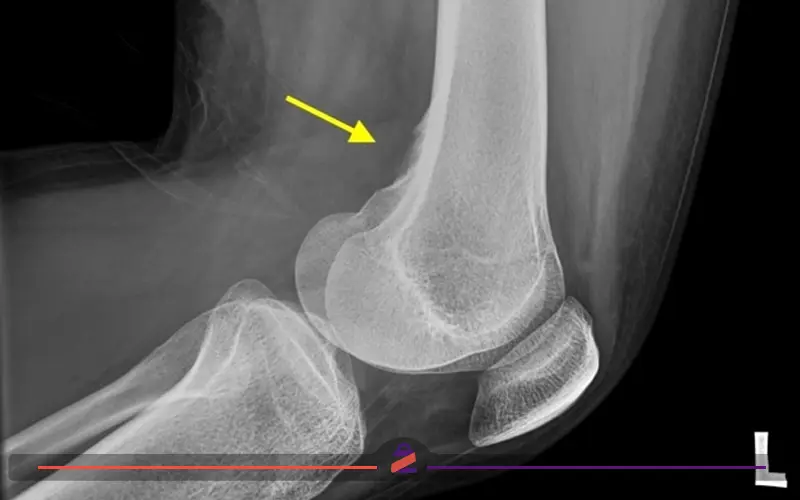

جراحی خار زانو؛ خارهای استخوانی در زانو برآمدگیهای استخوانی هستند که در مفاصل زانو، زمانی ایجاد میشوند که فشار بین استخوانها به دلیل کمبود غضروف افزایش یابد. به خارهای استخوانی استئوفیت نیز میگویند. خارهای استخوانی در زانو میتوانند باعث درد شوند و تحرک مفصل را محدود کنند، در نتیجه انجام فعالیتهای روزمره مانند راه رفتن، چمباتمه […]